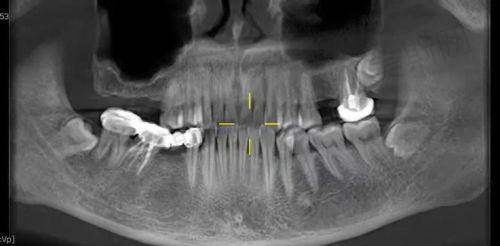

作为杭州本土有名连锁口腔品牌——杭州牙科医院集团在临平区的核心布局,临平口腔院区以三家分院(临平口腔医院、城南口腔医院、城北口腔医院)为支点,构建起覆盖临平全域的高品质口腔医疗服务网络。依托集团18年品牌积淀与北大、华 西口腔硕博骨干医生团队资源,院区整合数字化种植、个性化正畸、儿童特色口腔、美学修复等全科室诊疗能力,配备德国西诺德综合治疗椅、朗视CBCT、ITero数字化扫描仪等国内外精良设备,成为临平区规模领跑、技术实力强、口碑卓著的口腔健康管理优选机构。

诊疗特色方面,院区首创“数字化精细诊疗体系”,通过3D导板种植技术实现术中零误差植入,借助ITero扫描仪5分钟呈现矫正成效预见,结合DSD数码微笑设计打造自然美观的修复方案。环境上采用“家庭式温馨诊疗空间”设计,独立诊室保护隐私,儿童专区配备游乐设施与卡通主题诊室,有效缓解患者看牙焦虑。